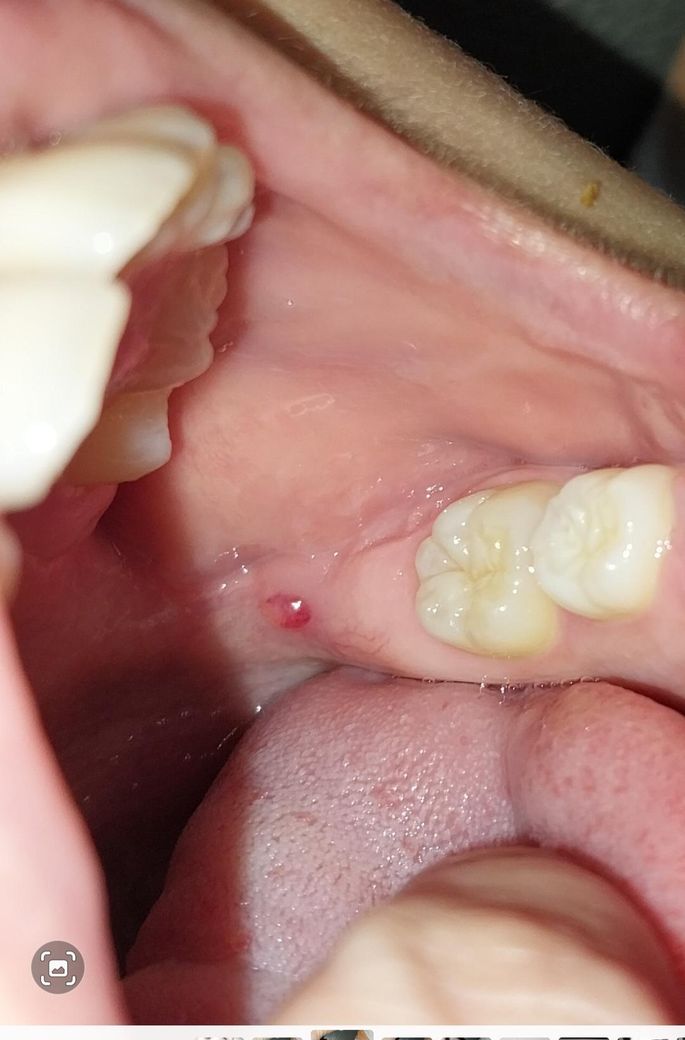

아이 입속에 이상한게 났는데 뭔지 궁금해요.

초4아이 입속에 빨갛게 뭔가가 났는데

커졌다가 줄었다가 하면서 거슬린다고 합니다

통증은 딱히 없다고 하는데 저게 뭔가요?

아이 말로는 줄곧 저자리에 뭐가 튀어나와있어서 커졌다 작아졌다 했던것 같다고 하는데

본인이 그동안 봤을때는 그냥 살색이었는데 오늘보니 빨갛게 되었다고 하네요.

• 1번 째 사진

아마도 자극에 의해 상처가 나는 것으로 보입니다. 아니면 깨물려 상처가 나면 저런식으로 물집 같이 생기기도 합니다. 그냥두면 없어질 것으로 보입니다.

단순 잇몸에 물집이 잡힌거 같습니다. 터트리면 될것같으니 너무 걱정하지 않으셔도 될것같습니다.

사진으로 봤을 때는 점액종으로 보입니다. 점액종은 점막 조직이라고 과연 자극을 받았을 때 점액 내부에 조직 액이 차면서 생기게 됩니다. 그게 문제가 되는 것은 아니며간단히 제거할 수도 있습니다. 자세한 확인을 위해서 치과에서 진료를 받아보는 것을 권해드립니다.